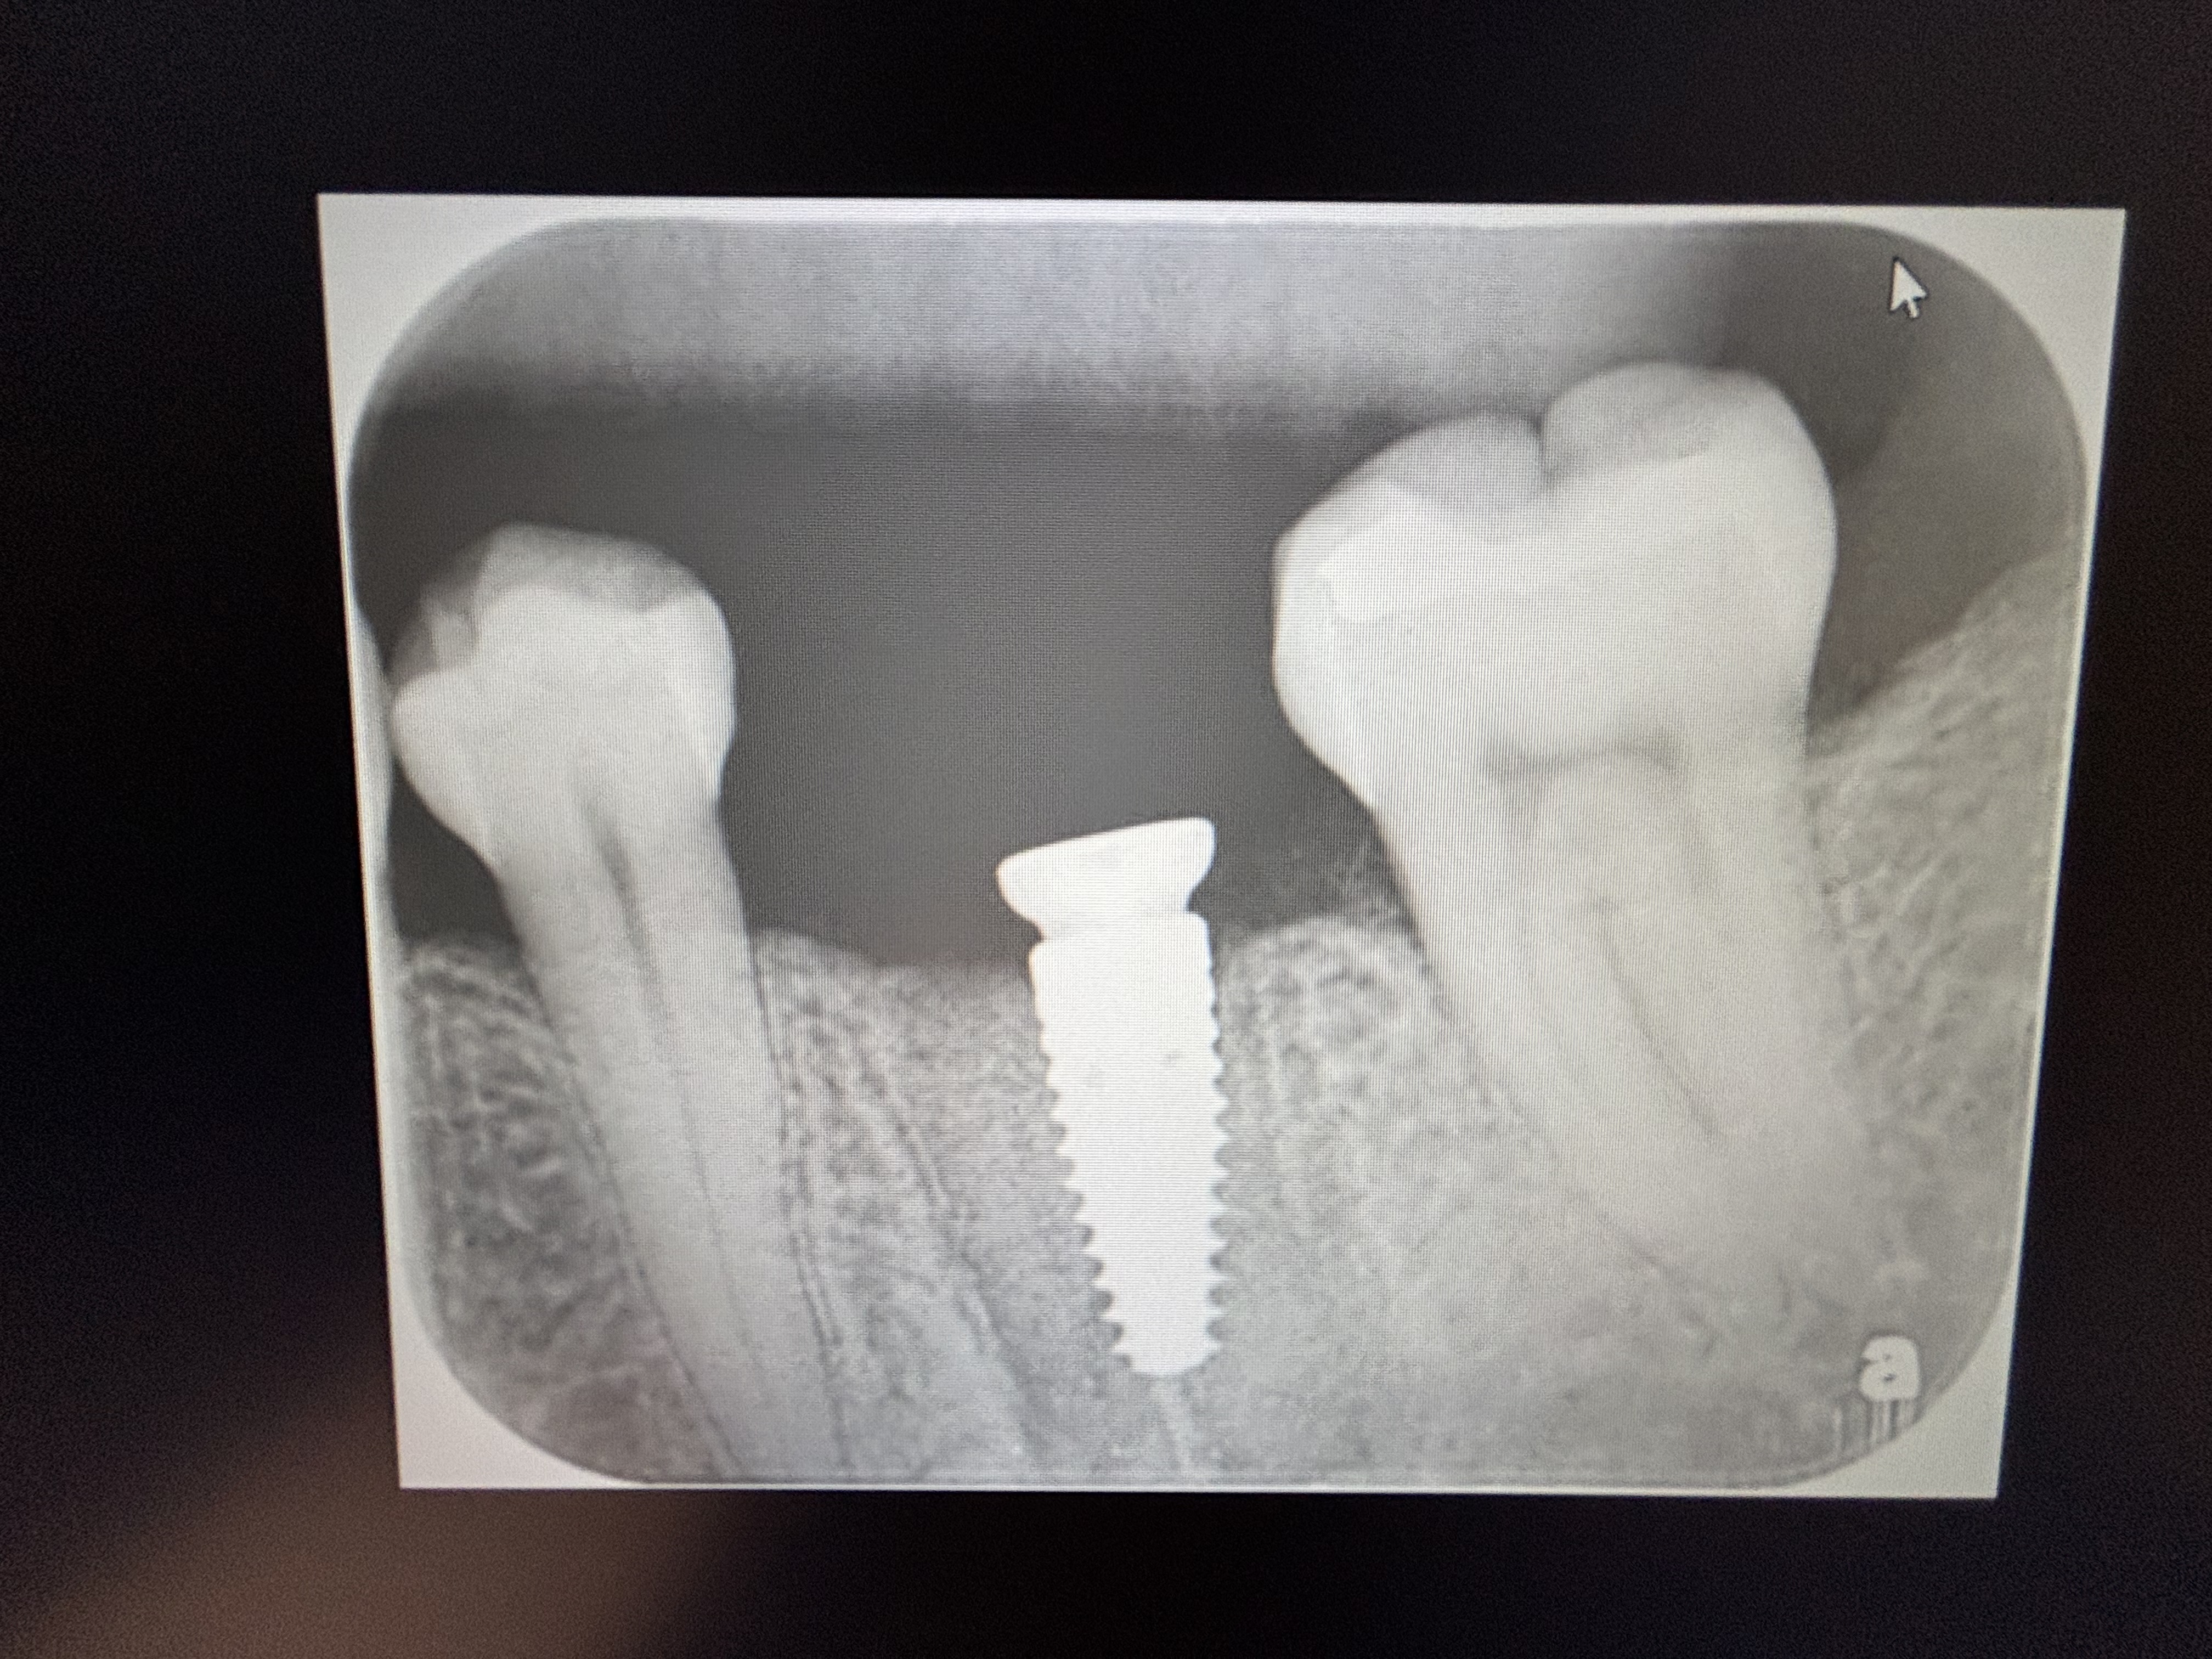

Implants placed too close: Is this restorable?

I am feeling really humble. I’ve placed multiple implants and thinking this should be a straightforward case. I was wrong. I know it’s poorly planned and freehand did not go well. Are these restorable? Should I explant and redo? If I do remove these, how easy is it to remove these?